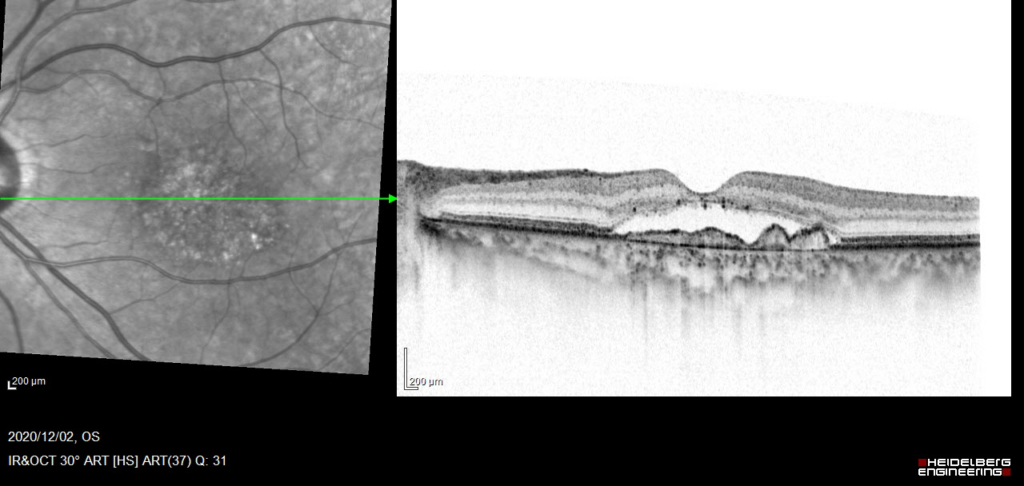

中心窩に灰白色病変がみられる。

漿液性網膜剥離 Serous Retinal Detachment(SRD)がみられる。RPEは不正に隆起し、double-layer sign(RPEを示す高反射層とそれより外層にみられる高反射層の間に間隙がみられる)がみられ、CNVの存在を示す。